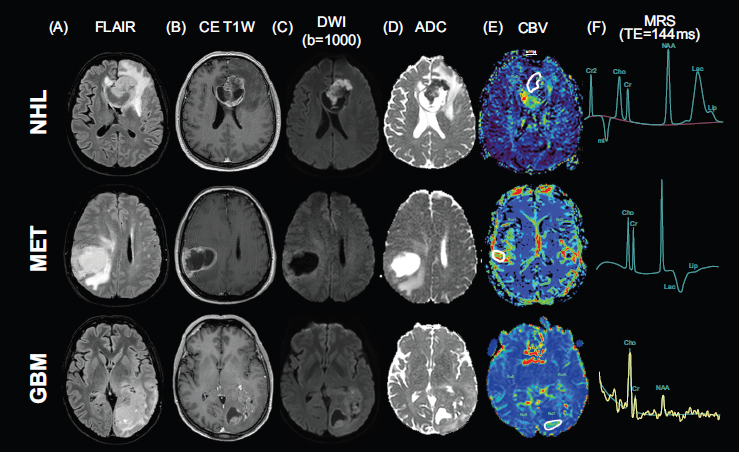

Example of conventional MRI findings in the three most common adult brain tumor types. Three examples of conventional MRI findings in non-Hodgkin lymphoma (first row), single brain metastasis (second row), and wild-type glioblastoma (third row): A) FLAIR imaging; B) post-contrast T1w imaging; C) b-1000 DWI and D) relative ADC map; E) CBV map from DSC-PWI, with ROI placement (white continuous line); F) MRS metabolite spectrum (TE=144 ms).

MRI DICOM data from each examination were anonymized and locally stored. Quantitative variables derived from DWI, PWI, and MRS acquisitions encompassed: ADC values from the DWI sequence; CBV, CBF, MTT, and TTP values within the specific ROI from the DSC PWI acquisition; metabolite peaks, such as lipid-lactates (Lip-Lac), N-acetylaspartate (NAA), choline (Cho), and creatine (Cr), with their ratios from MRS acquisition. To minimize information loss, the above-mentioned quantitative variables derived from DWI, PWI, and MRS acquisitions were analyzed and plotted using CA [13]. PCA was performed for dimensionality reduction and exploratory data analysis, as it transforms a set of possibly correlated variables into a smaller set of uncorrelated variables called principal components (PCs). These components are linear combinations of the original variables and are ordered so that the first component captures the maximum possible variance in the data, the second captures the maximum remaining variance orthogonal to the first, and so on. Before PCA, variables were standardized by calculating their means and standard deviations, and then applying the standardization formula z = (x−μ)/σ. To determine how many PC to retain, a scree plot graph was obtained. To determine whether the differences among the three groups (NHL, GBM, and MET) were significant, the Kruskal-Wallis test was used. Finally, for relevant parameters, between-groups differences (NHL vs. GBM, GBM vs. MET, and MET vs. NHL) were tested using the Wilcoxon signed-rank test. An original p-value of less than 0.01 was set, followed by Bonferroni correction to adjust for multiple comparisons. For all analyses, a final significance level of p = 0.0011 (Bonferroni-corrected) was established. Statistical analyses were performed using the XLStat package v.2019. An example of an MRI of the three malignant brain lesions included in the analysis is shown in Fig. (1). Demographic data and the prevalence of final histological diagnoses in our sample are summarized in Table 1.